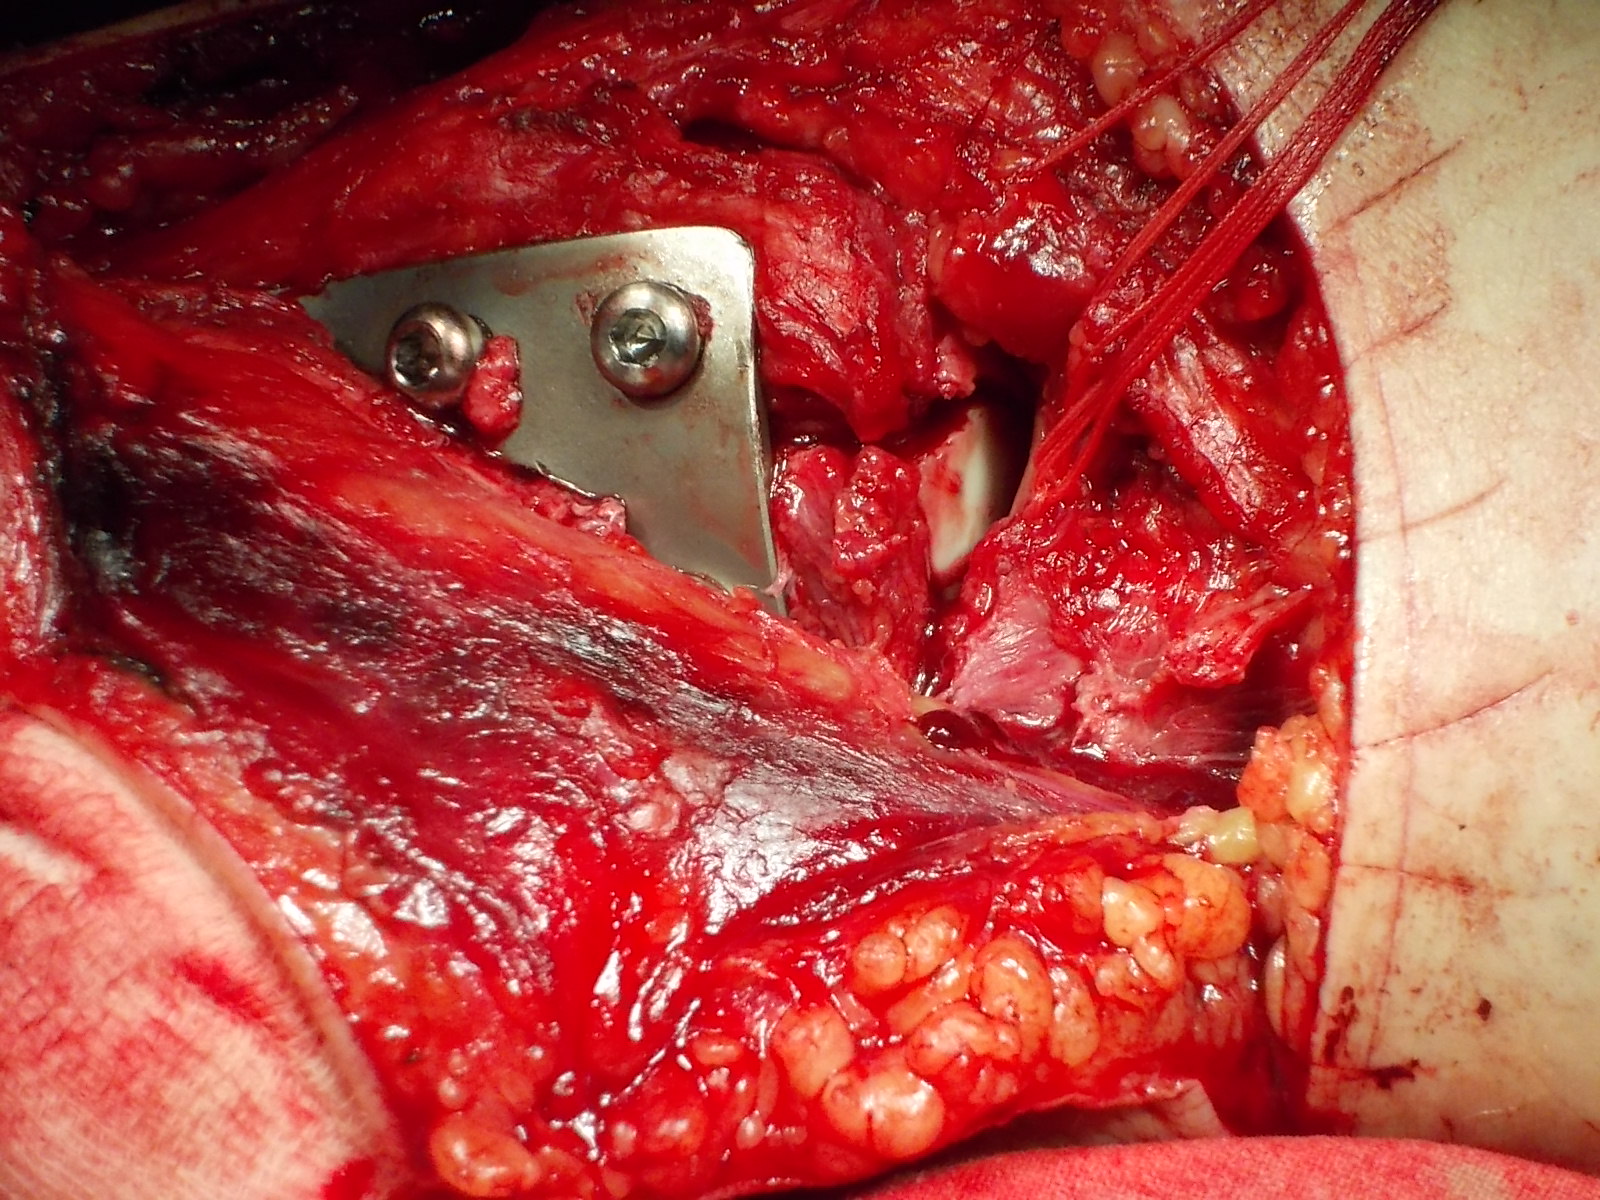

Операция - открытая репозиция, остеосинтез большеберцовой кости опорной пластиной с костной ксенопластикой маетриалом "Остеоматрикс". На контрольных снимках в три и шесть месяцев имеется консолидация перелома, миграции фиксатора нет, имеется остеоинтеграция ксенопластического материала. Функция коленного сустава полная.